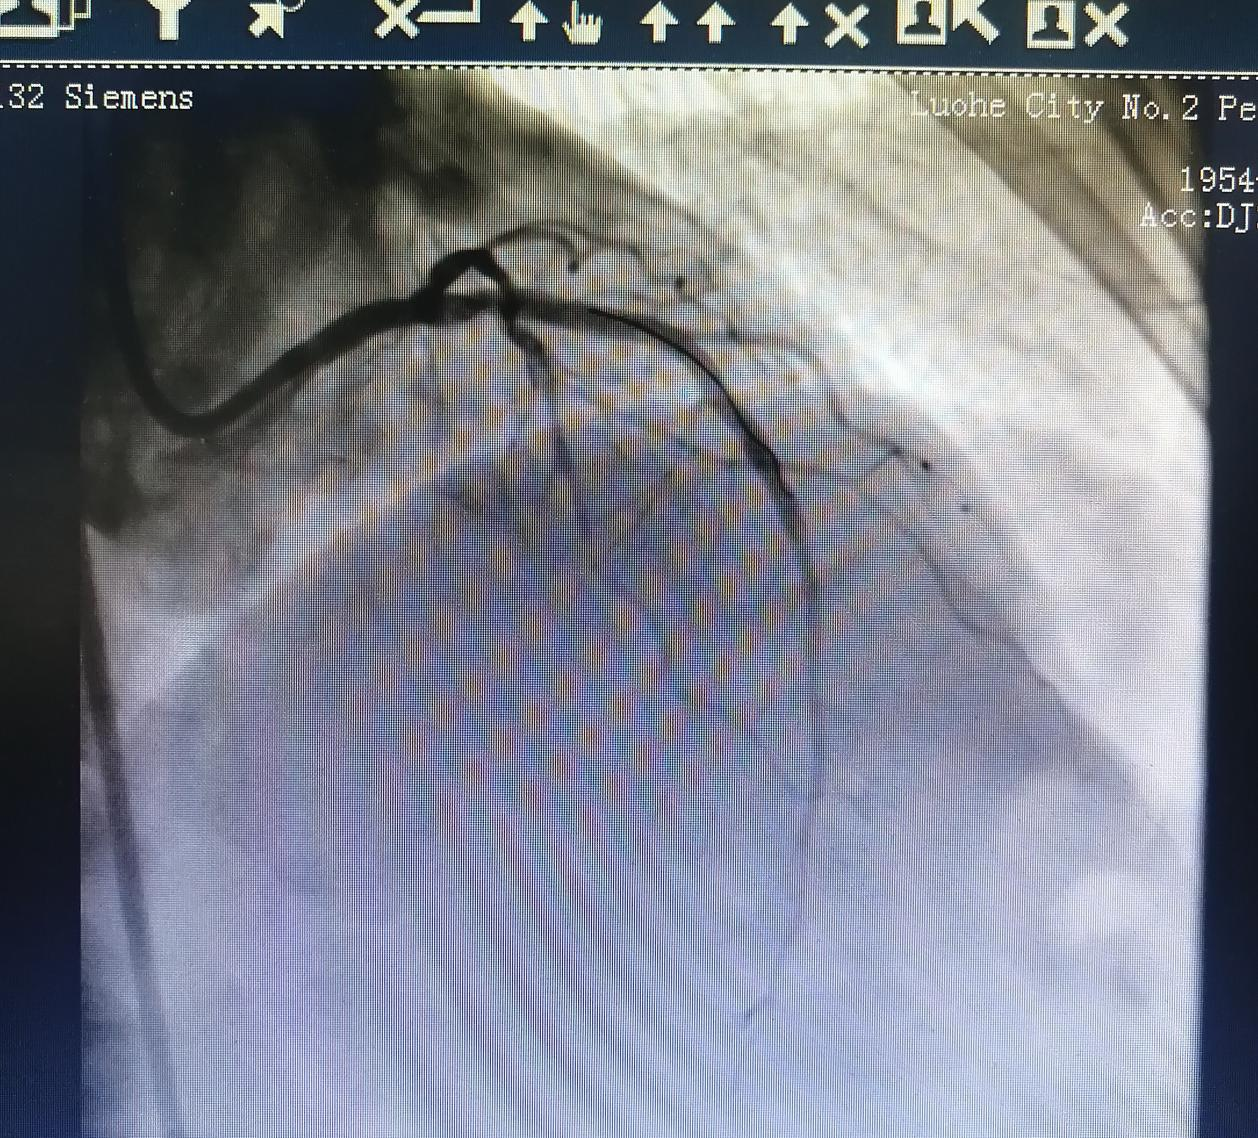

術(shù)后:

術(shù)后,張阿姨胸悶癥狀較前有所改善。

經(jīng)過(guò)充分的評(píng)估和準(zhǔn)備,在金叔宣教授的指導(dǎo)下,心血管科內(nèi)科介入團(tuán)隊(duì)為張阿姨制定了個(gè)體化的手術(shù)治療方案,即行血管內(nèi)超聲+冠狀動(dòng)脈旋磨術(shù)+冠脈支架置入術(shù)。